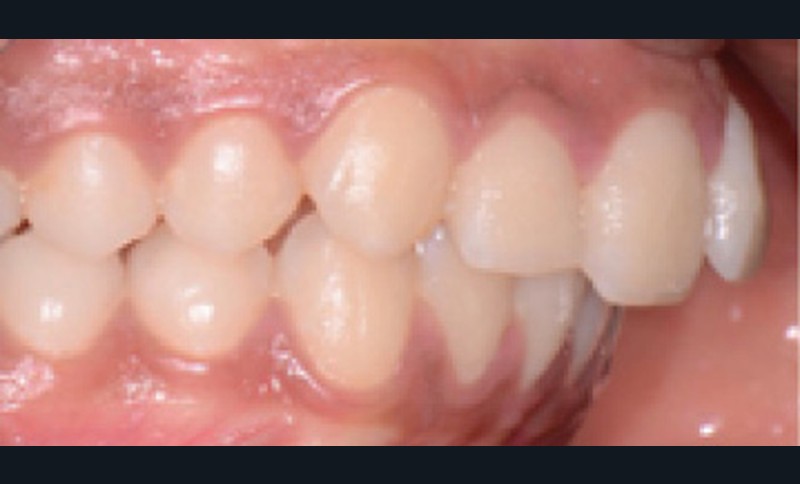

Examen clinique (fig. 1 à 7)

Sur le plan dentaire, elle présente une classe II d’Angle complète, une supraclusion de 4 mm et un surplomb de 6 mm ne correspondant pas au décalage de classe II molaire.